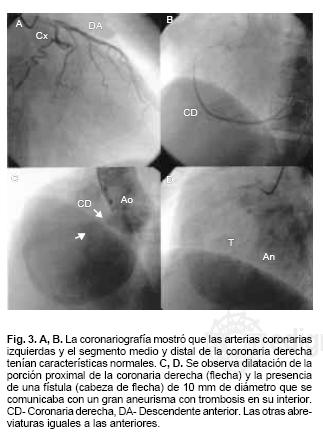

Presentamos el caso de un varón de 58 años, con antecedentes de contusiones múltiples en hemitórax lateral izquierdo, 3 años antes inició con disnea progresiva de medianos a grandes esfuerzos y palpitaciones. A la exploración física con signos vitales estables, plétora yugular GIII, campos pulmonares con murmullo vesicular normal, ruidos cardíacos rítmicos, desdoblamiento fisiológico del 2do ruido, soplo regurgitante tricuspídeo I/IV, soplo continuo audible en foco aórtico y hepatomegalia. El electrocardiograma mostró ritmo sinusal, crecimiento auricular derecho y extrasístoles auriculares frecuentes. La radiografía de tórax con dilatación de la aurícula derecha. En el ecocardiograma transtorácico 2D se observó dilatación de la aurícula derecha (AD), imagen de aspecto quístico con diámetro de 8.4 x 8.0 cm con trombo y flujo lento en su interior. Las valvas de la tricúspide de aspecto normal pero desplazadas hacia la parte posterior e insuficiencia tricuspídea ligera. La función sistólica ventricular izquierda fue normal. El ecocardiograma transesofágico multiplanar confirmó los hallazgos descritos y mostró también dilatación de la porción proximal de la coronaria derecha, la cual se comunicaba a través de una fístula con un aneurisma que contenía trombo en su interior (Fig. 1A, B, C y D), el cual a su vez drenaba a la aurícula derecha (Fig. 2A y B). El cateterismo cardíaco reportó tronco coronario izquierdo, descendente anterior y circunfleja sin lesiones, coronaria derecha con una gran dilatación de su porción proximal y fístula de 10 mm de diámetro que se comunicaba con el aneurisma, el cual drenaba a la aurícula derecha (Fig. 3A y B). El paciente fue llevado a cirugía, que confirmó los hallazgos descritos (Fig. 4A y B). Se efectuó aneurismectomía de la arteria coronaria derecha, trombectomía intraaneurismal, restablecimiento del flujo de la CD por puente venoso de safena interna a la aorta ascendente y plastía de la aurícula derecha con reconstrucción de su pared anterior (Fig. 5). Actualmente se encuentra en clase funcional I.